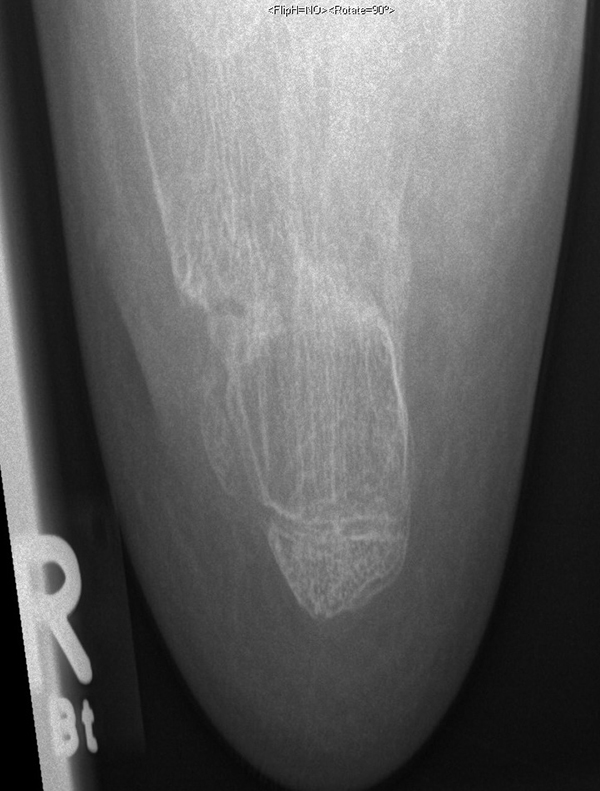

Welche minimalinvasiven fußchirurgischen Techniken in der Versorgung von Kinder- und Jugendfüßen geeignet und welche Indikationen sinnvoll sind, ist im Vergleich zu ausgewachsenen Füßen leicht abweichend. Hauptursache hierfür sind die Wachstumsfugen (Abb. 1).

Abb.1 a-b: Beispiel einer noch offenen Wachstumsfuge im dorsalen Bereich des Calcaneus: (a) Alter 6 und (b) Alter 9 Jahre.

In der Regel bestehen aktive Wachstumsfugen bei Mädchen bis zum 12. und bei Jungen bis zum 14. Lebensjahr, mit Abweichungen von einem Jahr nach unten und nach oben. Präzise Informationen unter anderem darüber gibt das präoperative Röntgenbild (Abb. 2).